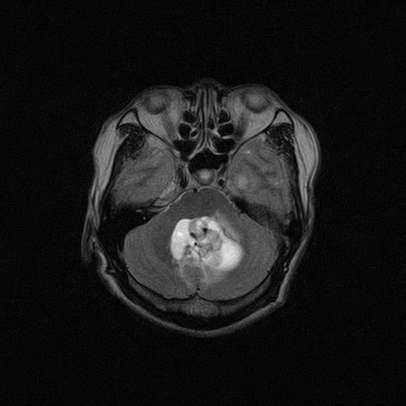

标题: MRI2064:少见病例。男性52,视力下降多年。 [打印本页]

标题: MRI2064:少见病例。男性52,视力下降多年。

四脑室区见混杂信号占位影,脑室系统扩张明显,临近结构显著受压称位,患者52岁,多考虑室管膜瘤可能性大

定位;脑室内富血供占位

1,脑室内血管母细胞瘤。

应该是来源于小脑蚓部的占位,如血管母细瘤或星形细胞瘤

小脑血管母细胞瘤.并外压性脑积水.

小脑蚓部胶质脑膜瘤突入四脑室;肿瘤内见血管流空信号和钙化信号.

比较典型的脉络丛乳头状瘤并脑积水,鉴别小脑蚓部血管母细胞瘤。